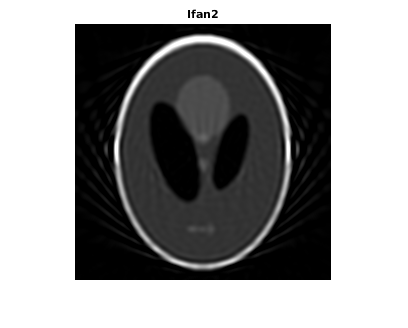

Восстановите изображение из данных о проекции луча вентилятора с помощью ifanbeam . В каждой реконструкции совпадайте с интервалом датчика вентилятора интервалу, используемому, когда данные о проекции были созданы ранее. Пример использует OutputSize параметр, чтобы ограничить выходной размер каждой реконструкции совпадать с размером оригинального изображения P . В выходе отметьте, как качество реконструкции поправляется как количество лучей в увеличениях проекции. Первое изображение, Ifan1 , был создан с помощью 2 интервалов степени лучей; второе изображение, Ifan2 , был создан с помощью 1 интервала степени лучей; третье изображение, Ifan3 , был создан с помощью 0,25 интервалов лучей.

Ifan2 = ifanbeam(F2,D, ... 'FanSensorSpacing',dsensor2,'OutputSize',output_size); figure, imshow(Ifan2) title('Ifan2')